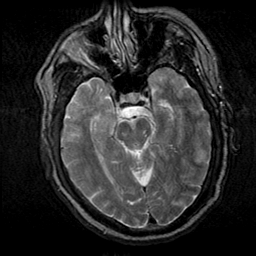

Subacute Stroke, overlay -- Slice #9

[Home][Help][Clinical] Slice 9